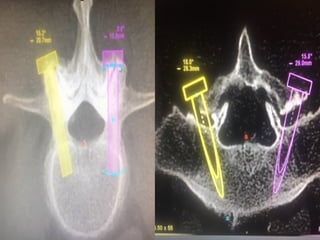

8-9-2018

Metastatic tumor

(prostate)

Spinal cord

decompresion

and

percutaneous

spondylodesia

Reconstructive surgery

Late post traumatic Lumbar instability and Kyphosis

Pre operative plan

Intraoperative correction and stabilization

Post operative x-rays

Lumbar – Sacral – Iliac

stabilization